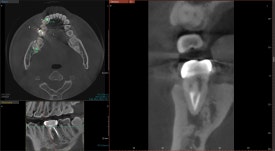

20250127

CT를 찍어봅니다.

아니나다를까,

뿌리 끝에 검은 빈 공간이 관찰됩니다.

염증 물질로 인해 뼈가 녹은 흔적입니다.